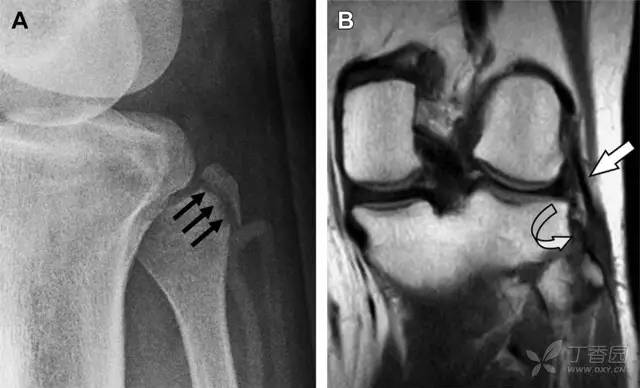

23 单纯肱骨大结节骨折

与其它肱骨近端骨折不同,单纯肱骨大结节骨折常发生于年轻人。肱骨大结节骨折常由撞击或剪切/撕脱损伤所致:

撞击包括直接撞击、肩峰撞击、上关节盂撞击(极度外展时);

剪切/撕脱损伤常发生于肩关节前脱位。

在常规前后位片上,大结节与肱骨头重叠,骨折不易发现,外旋位前后位片有助于诊断。

图 1 大结节骨折。(A)脂肪抑制序列斜冠状位 MRI,显示肱骨大结节线性骨折无移位(箭头)与周围骨水肿;(B)外旋位前后位(AP)片,证实大结节骨折(箭头),典型的骨折愈合过程中的骨吸收表现;(C、D)初诊时内旋位、外旋位前后位片,初诊时漏诊,仔细回顾影像,内旋伞下可见双密度影(椭圆),骨皮质中断(箭头)

24 无移位的桡骨头/颈骨折

多发生于摔倒时,手掌撑地,受到轴向、外翻应力所致。常规的前后位片容易漏诊,常需加拍内斜位、外斜位、桡骨头-肱骨小头位片。后脂肪垫可见(位于鹰嘴窝内,一般不可见)和/或前脂肪垫抬高常提示骨性损伤。

图 2 桡骨头骨折。前后位(A)和侧位(B)片示后脂肪垫抬高(黑色箭头),前脂肪垫抬高(白色箭头),呈「帆船征」,其它表现正常;外斜位(C)和桡骨头–肱骨小头位(D)示桡骨头关节内骨折线(虚线黑箭头)累及桡骨颈(虚线白箭头)

25 肩胛骨骨折

肩胛骨几何形状复杂,受到邻近其它骨性结重叠阻挡,且肩胛骨骨折少见,因此容易漏诊。当存在解剖变异时,诊断更为困难。

图 3 肩胛骨骨折正侧位片:由于骨块的叠加,(A)前后位片示「V」形高密度影(*),肩胛颈下方可见骨皮质碎片(箭头);(B)侧位片示骨皮质中断,骨折段移位,但由于肱骨的重叠遮挡,决断往往比较困难